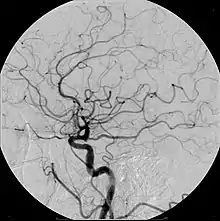

Quando administrado pela via intravenosa, é capaz de facilitar a identificação dos vasos sanguíneos, além de detectar alterações estruturais ou dinâmicas de funcionamento dos órgãos estudados, que em muitos casos, não seriam detectados de outra forma. Apesar de ter o potencial de alterar a função renal, na grande maioria das vezes o contraste iodado intravenoso o faz de maneira discreta e reversível, e por esse motivo, é amplamente utilizado pelo seu benefício, permitindo o diagnóstico e tratamento de condições de maior relevância para a saúde do paciente.